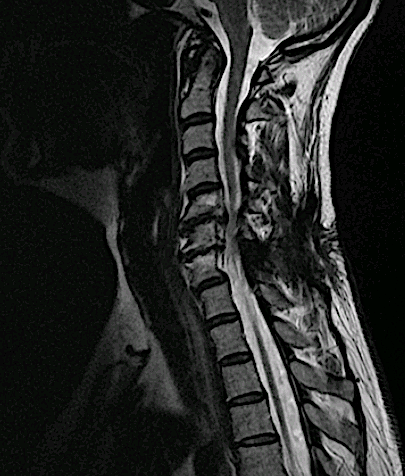

La lesión se ubicaba en el margen anterior de la lámina sin aparente afectación ósea en la RM cervical.

RM postoperatoria